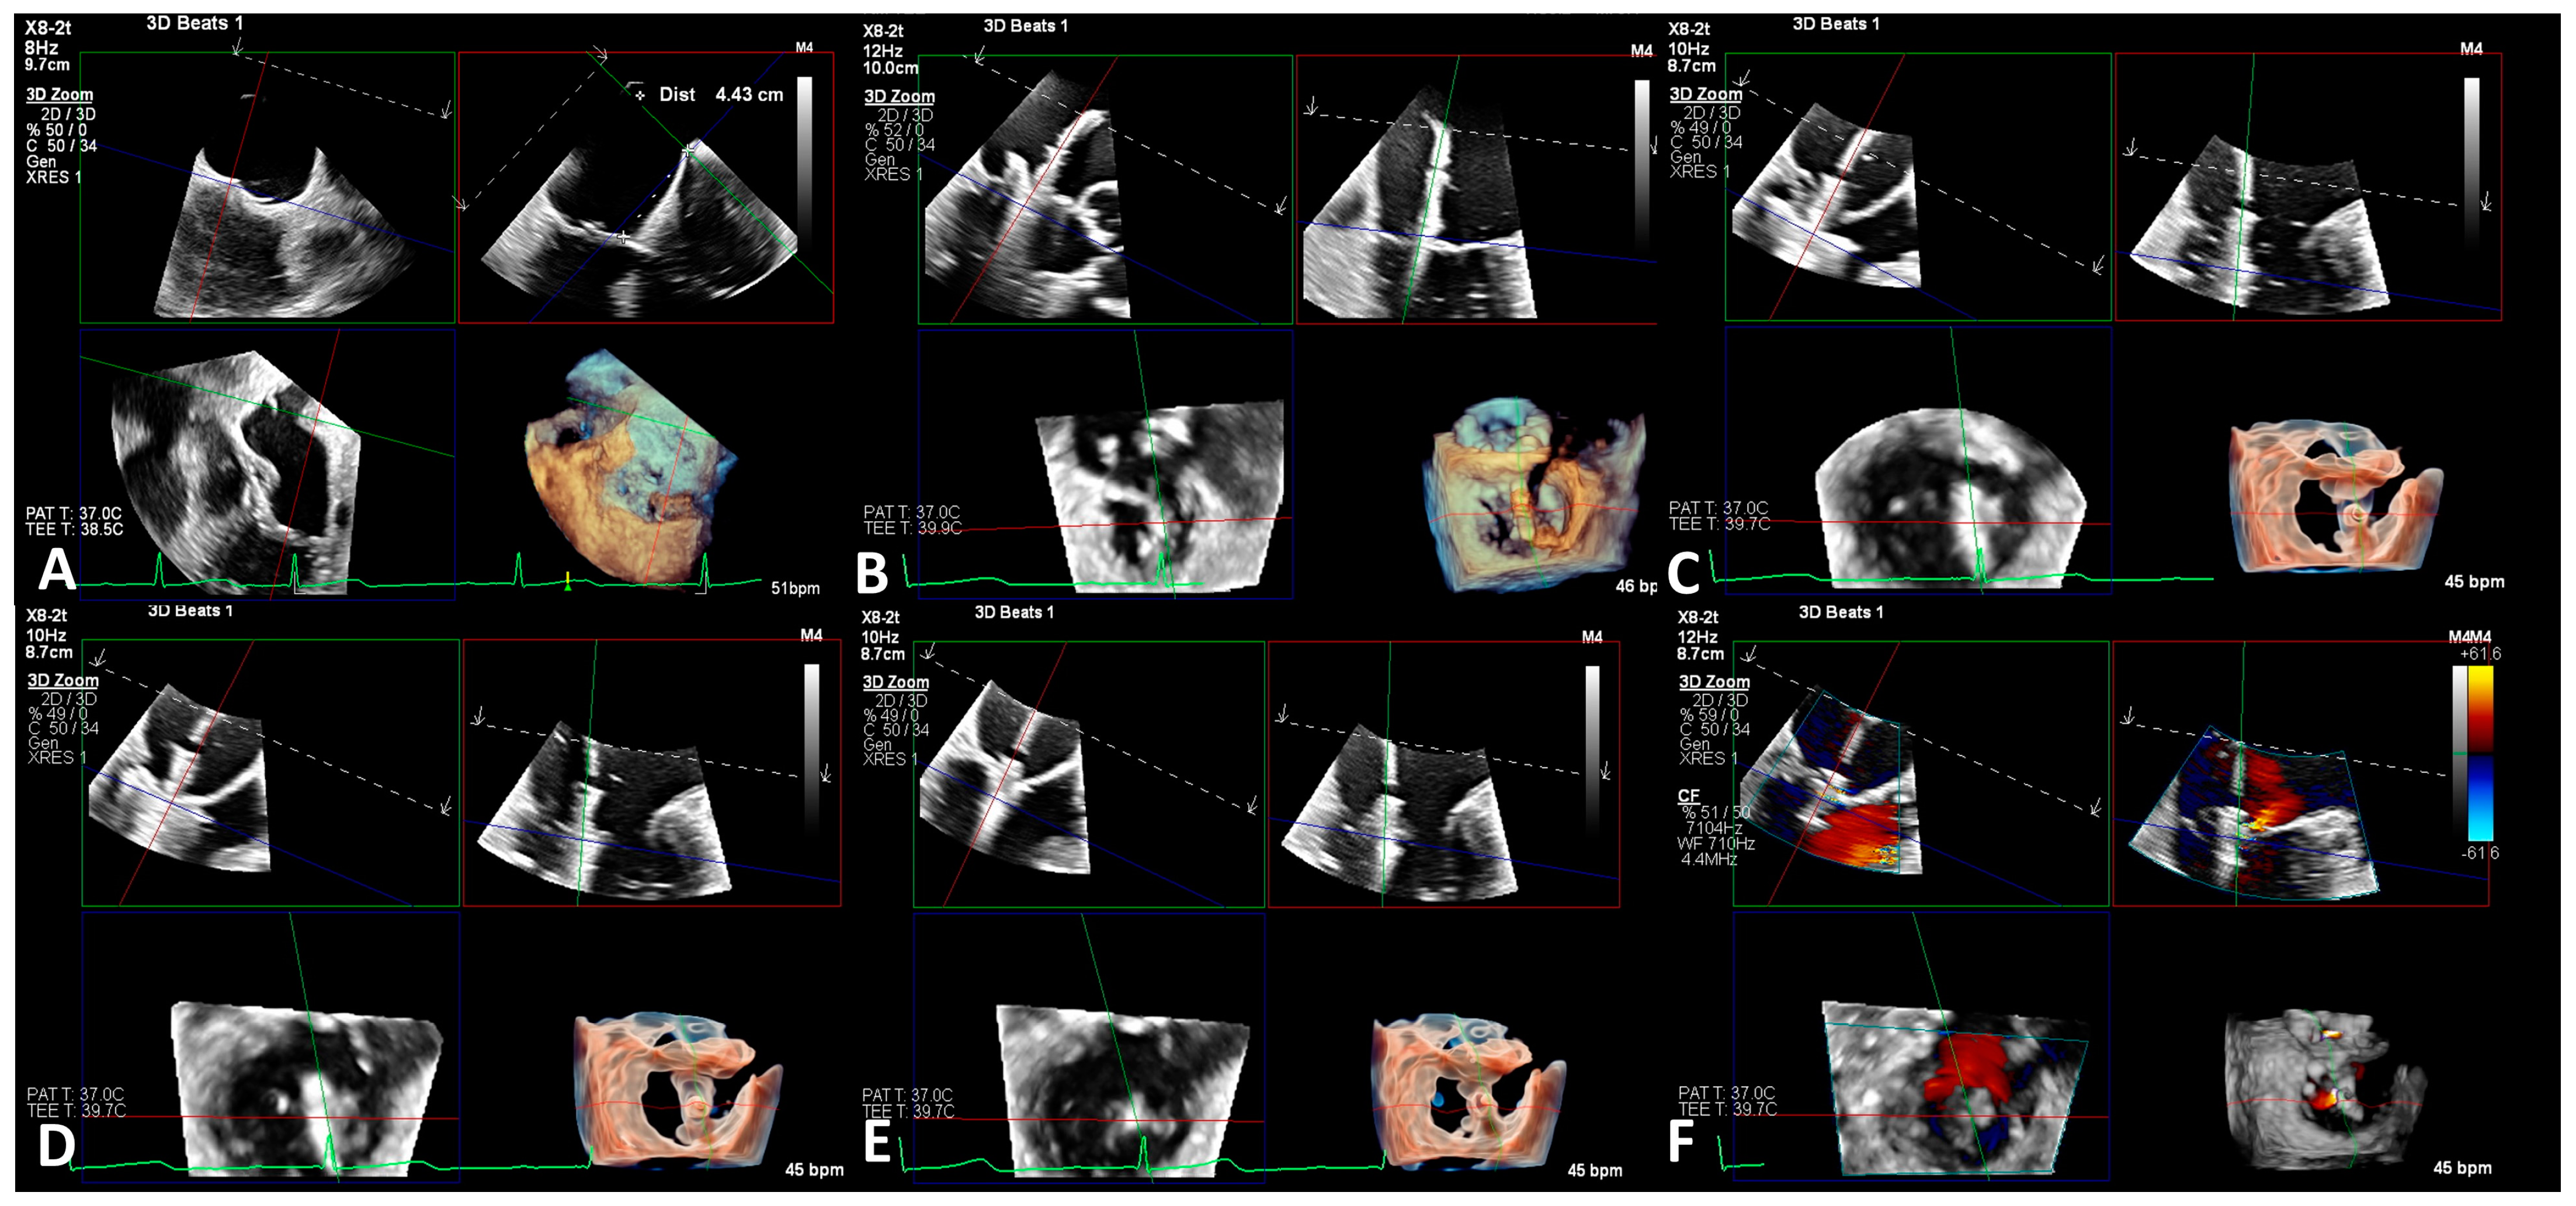

2.5. Imaging Evaluation

2.6. Procedure